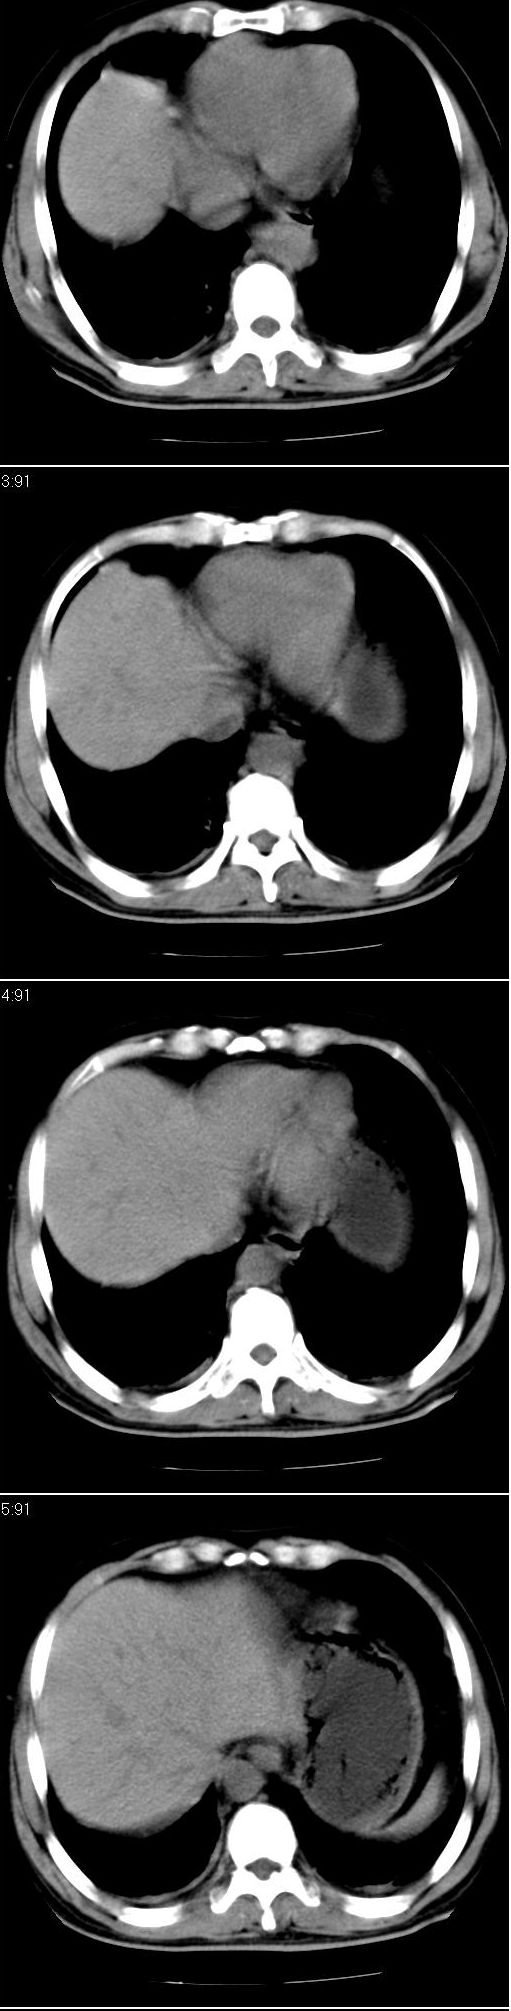

标题: CT13147:男,57岁。因胆结石阻塞性黄疸入院。 [打印本页]

标题: CT13147:男,57岁。因胆结石阻塞性黄疸入院。

男,57岁。因胆结石阻塞性黄疸入院。这是胆囊切除术后的照片,看看此片到底有什么问题。

胆总管有没有问题,尤其是肝门附近的胆总管?

肝门附近的胆总管轻度扩张 请楼主复习术前片

在手术切除胆囊的过程中,发现肝门部胆总管恶性占位,因为家属不同意手术,没有切除,能看出来么?

不是楼主提醒还真看不出来,肝内胆管扩张。略显僵硬。

肝内外胆管轻度扩张。楼主提示左右肝管合汇区域壁稍厚。胆总管末段壁似也稍厚有轻度强化。就现有资料诊断难。